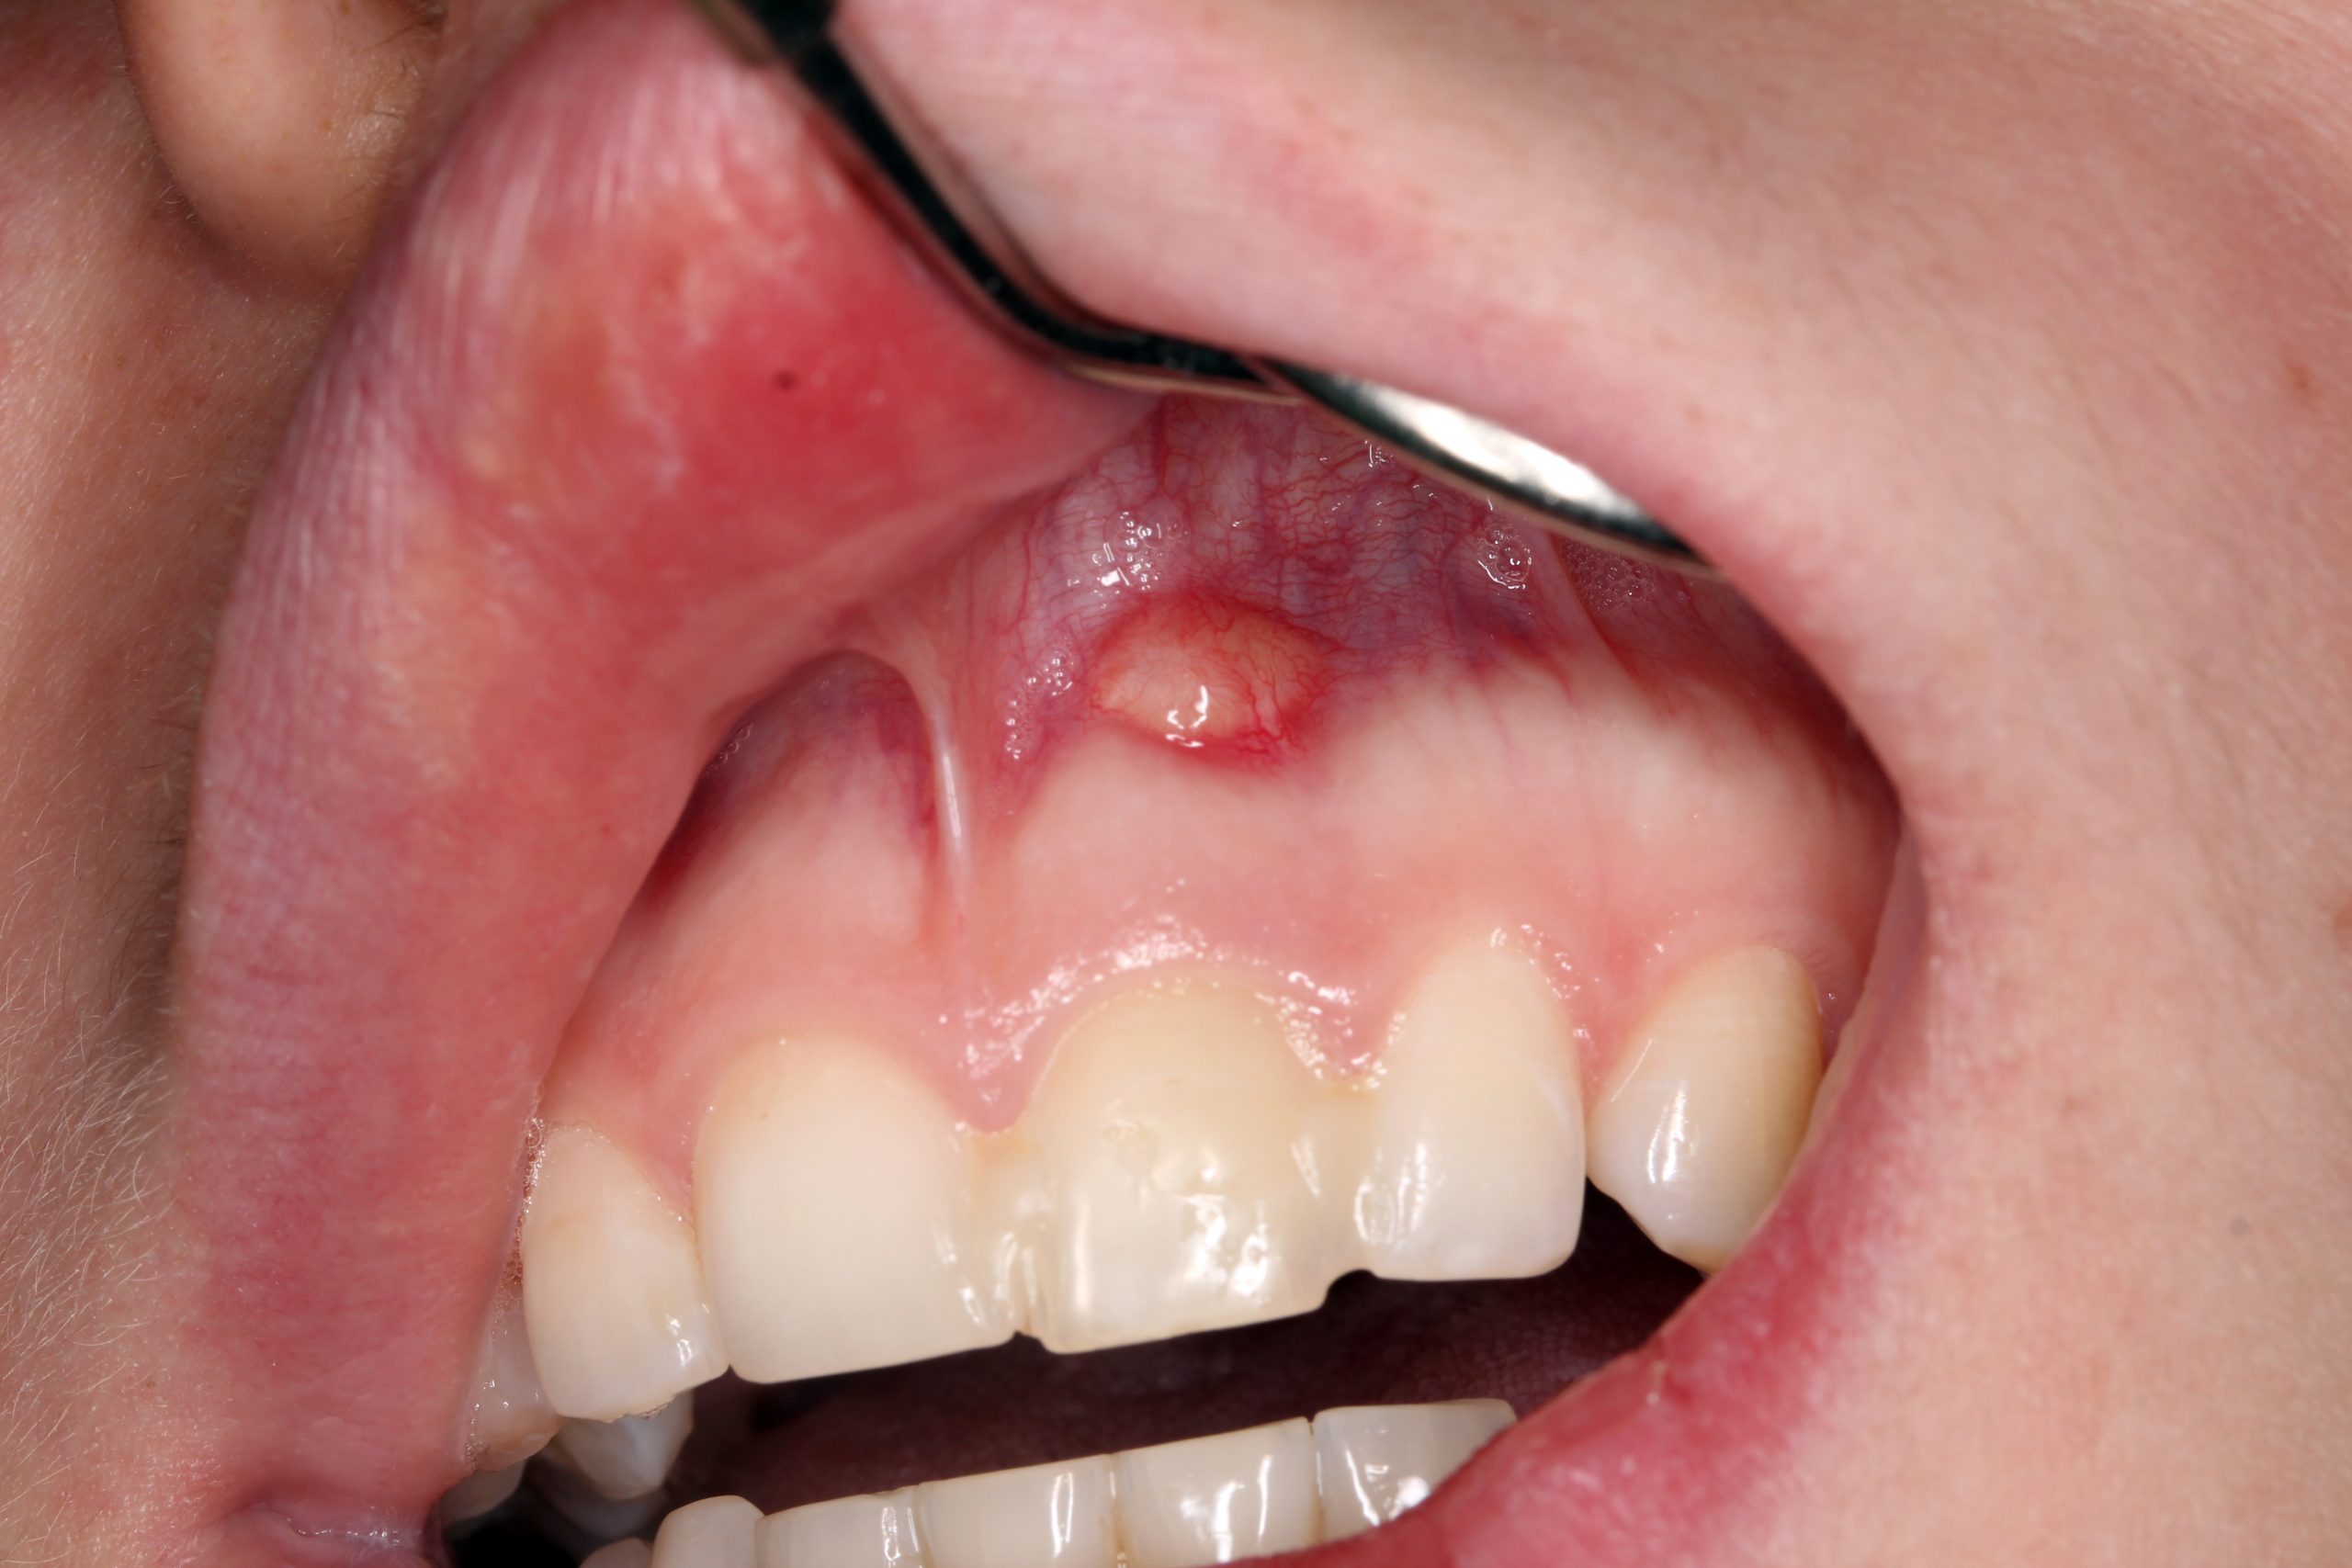

Eine 18-jährige Patientin klagte über eine wiederkehrende Fistel am Zahn 21. Bei einem Fahrradunfall vor fünf Jahren hatte sie sich eine Verletzung der Oberlippe und eine Subluxation des linken oberen Schneidezahns zugezogen. Nachdem das Weichgewebe genäht und der Zahn 21 repositioniert worden war, wurde sie von ihrem Zahnarzt weiterbehandelt. Vor vier Jahren kam es zu einer Verfärbung des Zahns. Mehrere endodontische Behandlungen folgten. Da der Zahn wackelte, wurde er mit den umgebenden Zähnen mittels eines Komposits verblockt.

Eine chronische Fistel in Regio 21. Der verblockte Zahn 21 mit einer unterschiedlichen Verfärbung. Die intraorale Röntgenaufnahme 21 bestätigte eine unvollständige endodontische Behandlung sowie eine teilweise Wurzelresorption.